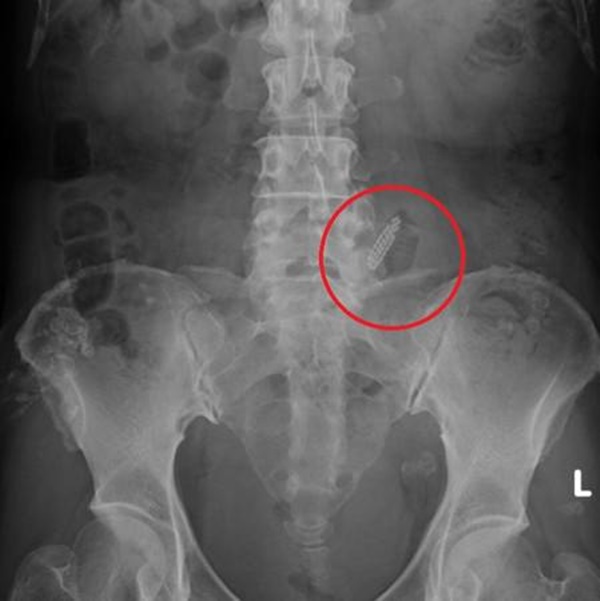

Khi nghe bệnh nhân nói điều này, bác sĩ Li Weihao đã rất sốc và nhanh chóng tiến hành kiểm tra phần dưới của nữ bệnh nhân. Bác sĩ Li Weihao nhận thấy âm hộ của cô đỏ và sưng lên, và có một vết xước cỡ móng tay. Có một vết thương ở âm đạo đã bị mủ, nhưng không phát hiện ra bàn chải đánh răng như nữ bệnh nhân kể. Hóa ra bàn chải đã lọt vào khoang bụng, kết quả siêu âm cho thấy bàn chải đánh răng bị mắc kẹt ở giữa bụng và ruột và đã kẹt được khoảng 5 ngày. May mắn thay, ruột không bị thủng.

Phim chụp X-quang của nữ bệnh nhân.

Sau khi phẫu thuật khẩn cấp, bác sĩ đã lấy được bàn chải đánh răng bị mắc kẹt trong khoang bụng của người phụ nữ và hút áp xe do bàn chải gây ra cũng như làm sạch khoang bụng. Sau ca phẫu thuật, bác sĩ tâm thần cũng xác nhận rằng nữ bệnh nhân đã mắc bệnh tâm thần, do đó sẽ có những ảo tưởng giết người và những suy nghĩ đặc biệt.